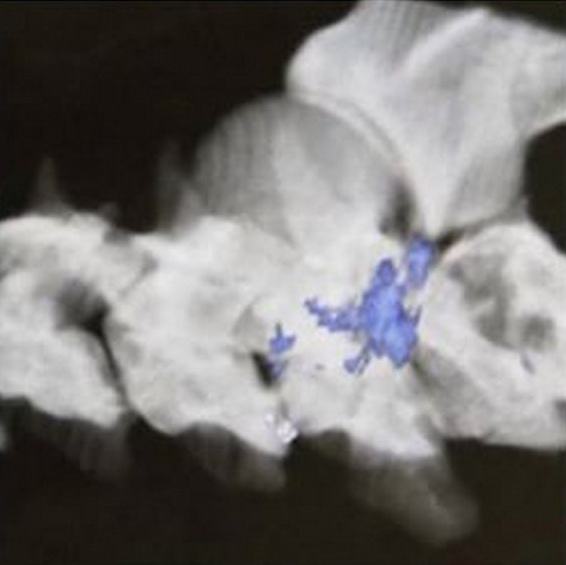

یک قلاده خرس به دلیل اصابت گلوله سلاح شکاری به نخاع زخمی شد که سه روز

پیش در پارک ملی کیاسر پیدا شد.

آهنگری با بیان اینکه به دلیل اصابت گلوله به نخاع حیوان از کمر به پایین فلج شده بود، گفت: طبق نظر دامپزشک معالج اگر این خرس بعد از اصابت گلوله سریع پیدا میشد، احتمال نجاتش بسیار زیاد بود.